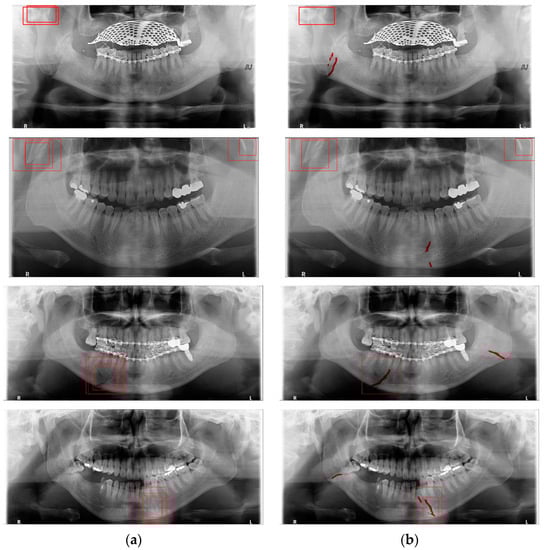

Deep learning networks such as Mask R-CNN, YOLOv4, and U-Net have been used to detect mandibular fractures using only panoramic images. The advantages of the three networks can be identified experimentally through panoramic mandibular fracture images. First, Mask R-CNN specifically marks the fracture area; however, it also marks fractures in areas that are not fractured, such as dark shaded areas in the panoramic image or gaps between teeth; therefore, the false diagnosis rate is higher than that in other deep learning networks. In YOLO, the location information for the six classes divided into anatomical structures is helpful to detect mandibular fractures. However, there are some undiagnosed fracture areas, other than the fractures of the condyle and coronoid process with clear characteristics and location. Unlike the above two deep learning networks, U-Net performs training by labeling fracture and panoramic images. When creating training fracture labeling data, the dislocated fracture area of the condyle fracture is difficult to label. Unlike YOLO, the side fracture area is weak, causing an increase in the misdiagnosis rate when learning by labeling a dislocated fracture. In Figure 17, the mandibular fracture detection results images of LAT YOLOv4 and U-Net with LAT YOLOv4 are compared. The panoramic images in the first and second rows demonstrate the advantages of YOLO and U-Net. While YOLO detects condyle dislocation fractures well, it does not detect angle fractures; however, U-Net detects angle fractures well. The panoramic images in the third and fourth rows show that the undiagnosed area is reduced by using U-Net for the angle area that the LAT YOLOv4 module does not diagnose. Because U-Net performs semantic segmentation, it is advantageous for the segmentation of fractures spread over a wide area. Consequently, the undiagnosed case in the middle of the mandible, where LAT YOLOv4 is weak, is somewhat supplemented by the U-Net module.

Figure 17.

The comparison of LAT YOLOv4 and U-Net with LAT YOLOv4 detection results. (a) LAT YOLOv4 (with red boxes), and (b) U-Net & LAT YOLOv4 (with red boxes and lines).